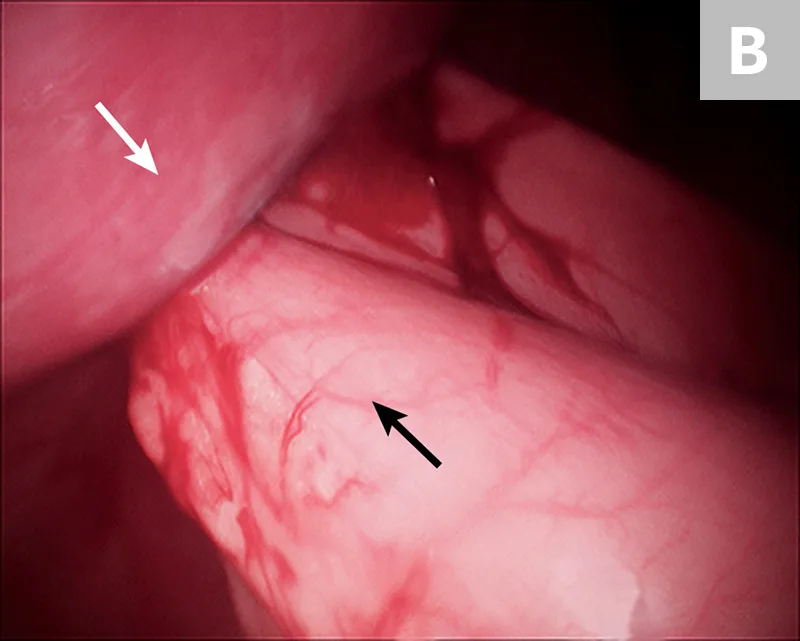

FIGURE 2

Cryptorchid testicle adjacent to the small intestine in the caudal abdomen (A) and elevation of the testicle using 5-mm grasping forceps before retraction through the port and extracorporeal ligation of the vascular pedicle (B)

After placement of a camera and abdominal insufflation, with the patient in dorsal recumbency, the caudal abdomen is explored, and the location of the testicle is confirmed (Figure 2A). A second port is placed to allow easy access to the testicle. The testicle is grasped (Figure 2B) and exteriorized through the instrument port. The vascular pedicle and ductus deferens are double ligated extracorporeally using routine techniques, and the ligated pedicle is returned to the abdomen. If necessary, the abdomen is re-insufflated and the procedure is repeated for the contralateral testicle. The pedicle is checked for adequate hemostasis, and the port incisions are closed routinely.